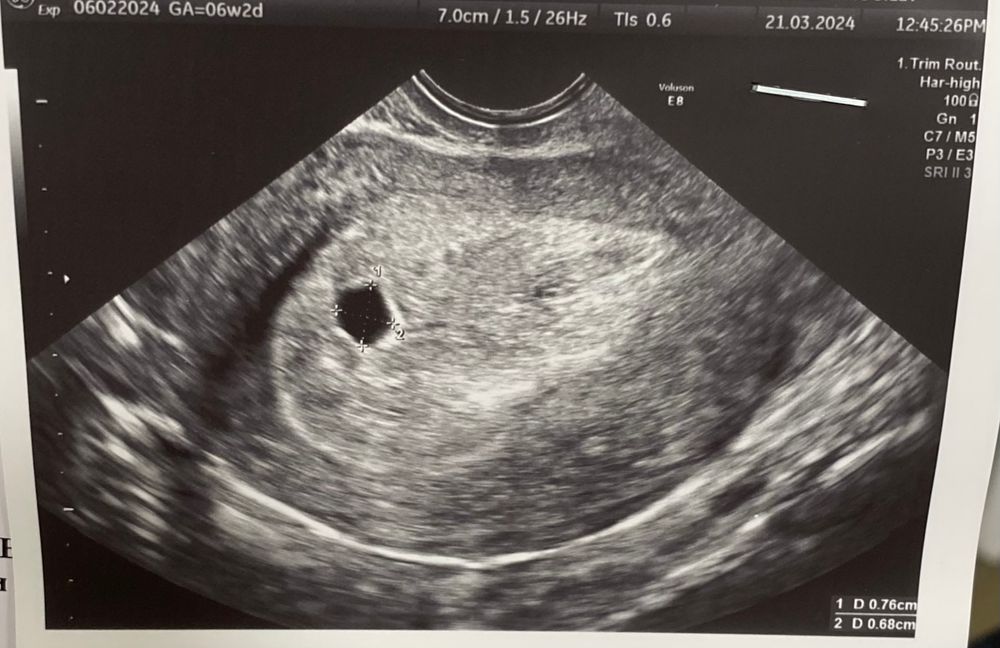

Анэмбриония?

Вообще, после визуализации ПЯТЬ через неделю должен появиться ЖМ. Объективно плодное выросло очень мало. Скорее всего да, это анэмбриония. Если вам сложно в это поверить и принять, вас никто насильно не заставит прервать беременность. Вы можете подождать еще 5-7 дней и повторить ультразвук

Насколько я помню, в прошлый раз у вас по узи все было довольно не плохо. Лучше ещё дней пять подождать. но по этому узи жм не видно😢

От поздней овуляции зависит только время визуализации пя. А у вас 8 дней назад было пя 4.7 мм, за неделю выросло всего на 2.9 мм. Это очень очень мало.

Мало выросло пя за 8 дней,в норме пя растет по 1 мм в сутки и за 8 дней с 4,7 должно было вырасти до 13 и появиться жм и зачатки эмбриона